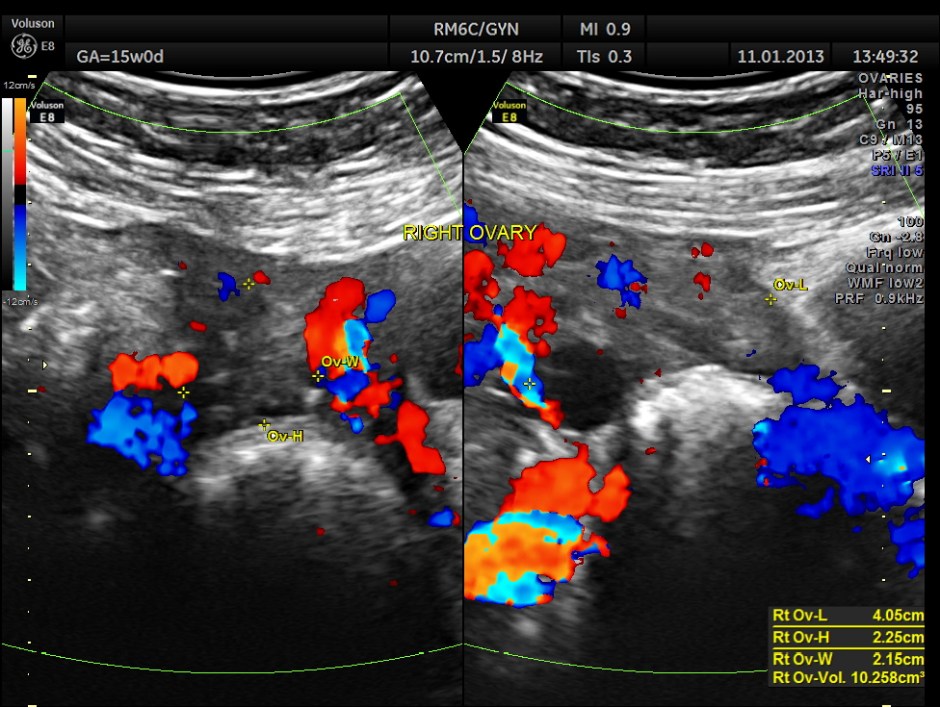

Right ovary was seen to be normal.